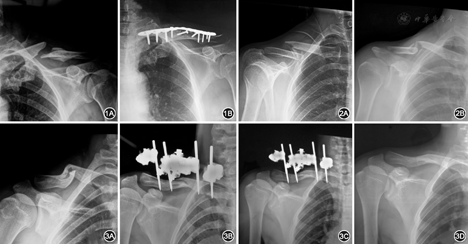

3组患者平均随访32个月,29例外固定架组患者,成功随访25例,失访4例,随访率86%。钢板固定组及非手术治疗60例患者均得到随访,随访率为100%(图1,图2,图3)。

A组最大并发症为针道反应及早期颈部活动受影响。B组最大并发症为内置物刺激症状及需二次手术取出。C组主要并发症为骨折畸形愈合(表3)。

A组、B组患者对肩关节外形满意度很高。C组患者对外观满意尚可,主要表现在双肩不对称及垂肩畸形(表4)。

A组出血量及手术时间明显少于B组(P<0.001)。B组在骨折断端之间解剖准确对位明显优于A组(P<0.001)(表5)。

锁骨中段骨折占所有锁骨骨折的80%[6],对于无移位中段骨折,非手术治疗仍是首选治疗方式。如有合并开放骨折、漂浮肩、神经血管损伤、完全移位或粉碎性骨折,首先考虑手术治疗[14,15,16]。在成人锁骨中段1/3移位的骨折治疗方法中,与非手术治疗相比较,手术治疗方法在减少骨折不愈合,畸形愈合,改善肩关节功能方面都取得了显著疗效[17,18]。至于使用外固定架或者切开复位钢板固定方式都各自有优缺点,外固定架属微创技术,对骨折块血运影响小,便于骨折愈合;不留长瘢痕;无需二次手术等优点[13]。钢板固定可达到完全解剖对位,无畸形愈合。但是内置物刺激及二次手术取除是其最大并发症[19]。应根据临床需要选择合适手术方法。

非手术治疗可以达到解剖复位,但是很难维持解剖对位直到骨折愈合。外固定架通过简单的经皮操作获得骨断端的良好复位且能维持直到骨性愈合。钢板固定完全达到解剖复位且获得骨性愈合。外固定架组骨折愈合时间所需约10周且达到96%愈合率。而非手术治疗组需15周左右且90%愈合率。对于锁骨中段移位骨折不愈合,外固定架技术治疗最终全部获得愈合[13,20]。非手术治疗优势在于骨断端血运未受到干扰、局部软组织完整,这为骨生长提供了有利生物学环境。而外固定架固定通过微创操作,对骨折断端血运及软组织未进行破坏,而且获得骨断端间的解剖或良好的功能复位,这为骨折愈合提供了良好的生物学及生物力学环境。而钢板固定具有完全解剖复位,无骨折畸形愈合以及早期功能锻炼等优点。最近文献报道手术与非手术治疗相比较,6周后随访发现,在肩关节功能方面手术组明显好于非手术组,但24周及5年后二者无差异。另外,患者对肩部外形及肩关节活动满意度来说,手术组高于非手术组[18]。

3组资料并发症对比来看,畸形愈合是非手术治疗的最大并发症,约占40%,主要表现是锁骨短缩、成角。其主要影响到肩关节正常生物力学[23,24]。本研究中没有具体测量平均短缩程度。至于短缩多少将影响到肩关节功能,目前还没有统一结论。短缩>2 cm或者短缩超过整个锁骨的9.7%,肩关节功能将受到影响[24,25]。通过非手术治疗短缩超过20 mm锁骨骨折,在随访中发现上肢功能活动未受到影响[26]。外固定架组最大并发症拆除外固定架之前,100%患者颈部活动、穿衣服等受影响。内置物刺激症状及二次手术取出看成是钢板固定组最多并发症,在肩关节外形来看,外固定架组患者满意率最高,达到96%;而非手术治疗组最低,仅为77%。